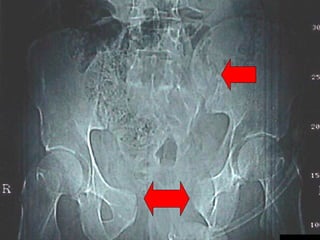

La lesione dell’apparato muscolo scheletrico che richiede  in ogni caso  un trattamento chirurgico con  priorità   assoluta  è la rottura dell’anello pelvico , che comporta una emorragia severa nel retro peritoneo e nella cavità peritoneale.

Immediata riduzione e fissazione del bacino

Se la risposta emodinamica a questo trattamento è buona il paziente verrà monitorato e potrà essere programmato un successivo intervento di osteosintesi definitiva

Angiografia e/o packing pelvico Se il paziente rimane instabile